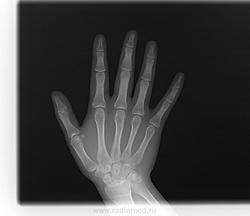

Девушка 16 лет, упала, беспокоит дискомфорт в области запястно-пястных суставов. В прошлом перелом "кисти" как она сказала, а что именно не помнит (по снимкам, полагаю, был перелом луча). Не нравится мне соотношение в л/з суставе. Есть ли подвывих какой?

Полулунная кость очень подозрительна. А более боковой проекции нет?

А про дискомфорт не ошиблись - то есть ладошка чешется, да?.. Снимки интересные - с подвыподвертом каждый немного.) Но тем не менее, всё при нём... на каждом. Возможно был перелом луча, а может, его строение аномальное слегка. Без архивных и бокового не заключал бы я перелома!.. И вывиха тоже.)

Перелом головки 4-й пястной кости. Согласен с Максималистом о необходимости снимка в боковой проекции.

По данному случаю мне кажется перерыв кортикального слоя по контуру со стороны локтя.